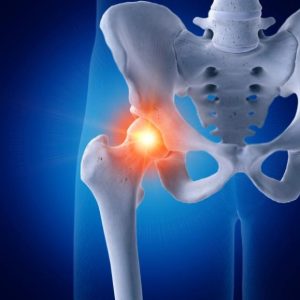

Les signes précoces d’usure d’une prothèse de hanche à connaître

La prothèse totale de hanche (PTH) est un traitement éprouvé pour les douleurs et la limitation fonctionnelle causées par l’arthrose ou d’autres pathologies de la